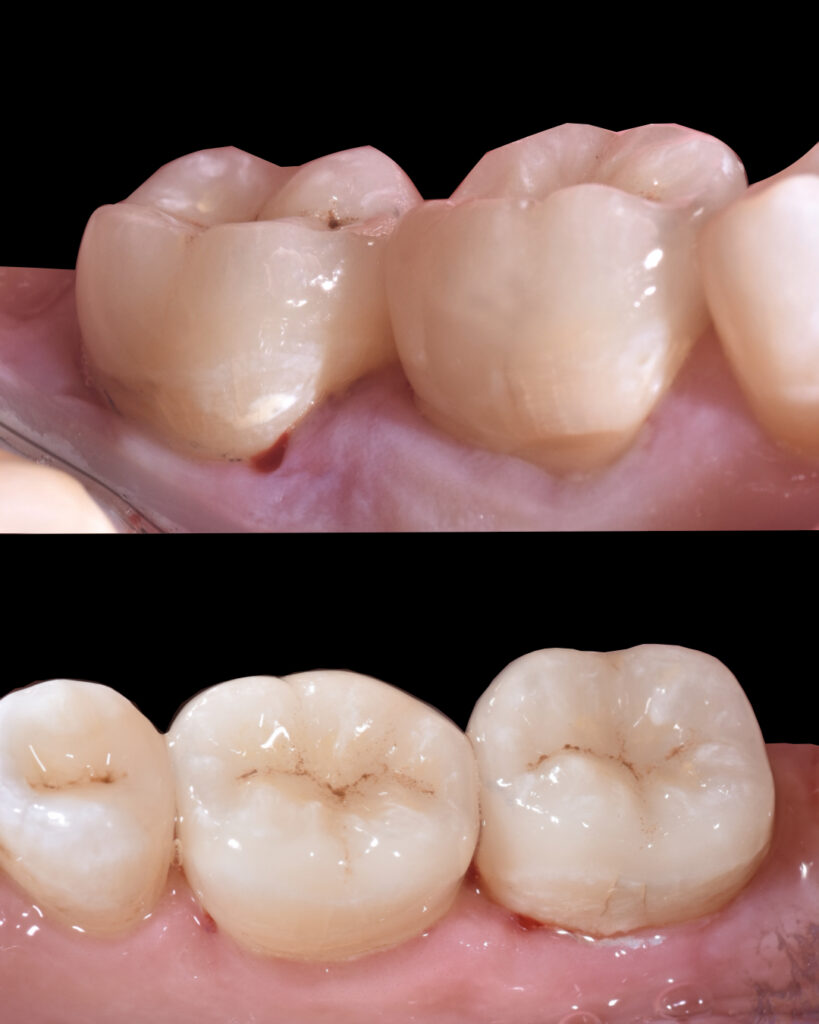

Tooth 3.6 was severely compromised and was managed with endodontic treatment, deep margin elevation, and an indirect adhesive restoration with full cuspal coverage using a lithium disilicate overlay.

Tooth 3.7 presented a large MOD carious lesion, with both distal cusps and the mesiolingual cusp structurally compromised.